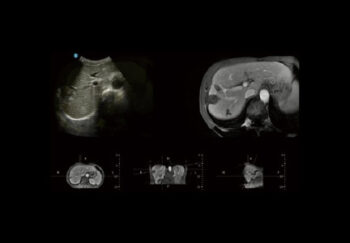

SonoFusion

Датчикт суурилсан дотоод магнит мэдрэгчээр тоноглогдсон тул гадны мэдрэгч хэрэглэх шаардлагагүй. Энэ систем нь хэт авиан өгөгдлийг CT/MR өгөгдөлтэй нэгтгэн, дүрсийг зэрэгцүүлэн харуулж, эмч нарт өвчнийг илүү цогц, нарийвчлалтай үнэлэх боломжийг олгодог.